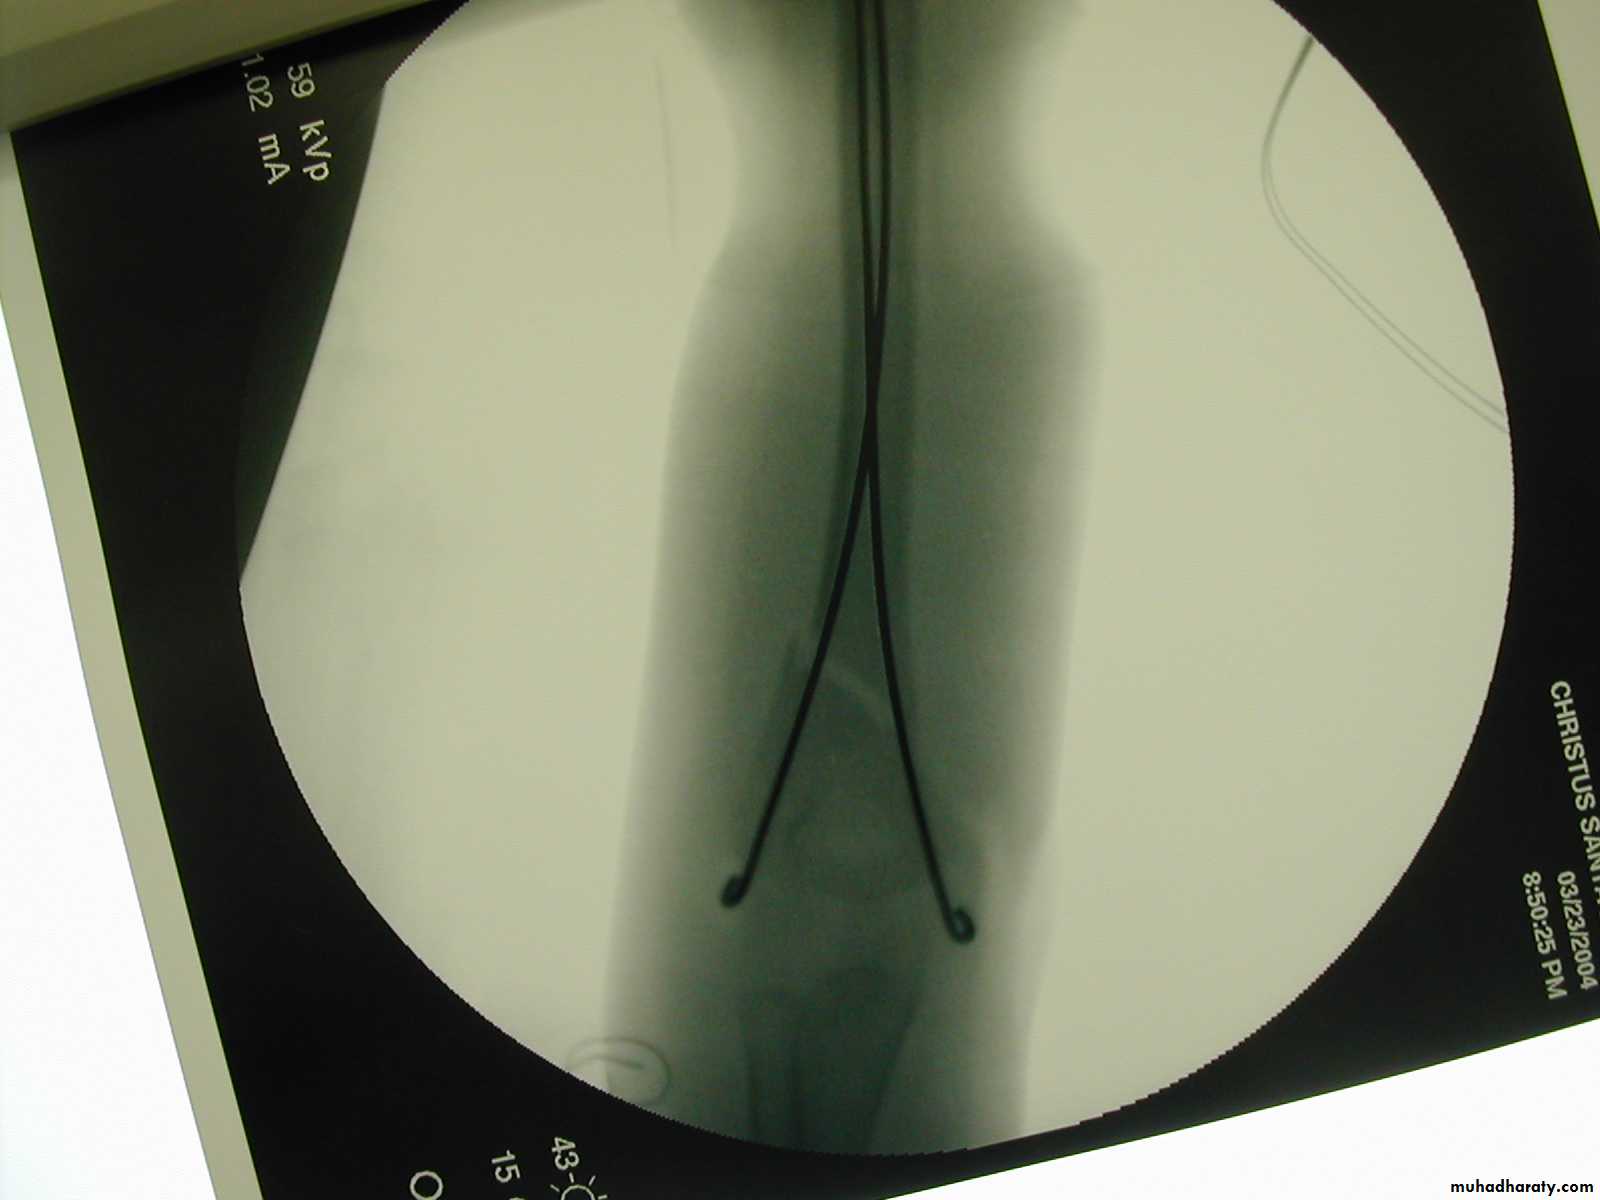

How about retrograde IM Fixation??

8 y.o. rolled over on an ATV

with mild closed head injuryClinical appearance

Only N-V deficit:

Anterior interosseous n. function weak

Radial A.

FCR Musc.Imaging Studies

How are we going to stabilize this boy’s fracture?

This is probably one of the few indication to use

Antegrade Flexible I M NailsOur Patient P.O.

Probably acts more

as an internal splintSix months post-operative

How is he doing clinically?